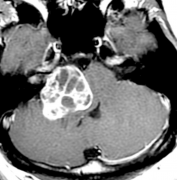

巨大听神经瘤术后2年随访,没有复发、无面瘫、无后遗症!

听神经瘤手术对于神经外科医生 水平要求极高 手术时医生常常进退两难 是为了全切肿瘤而牺牲正常神经功能? 还是保留神经功能但是切不干净? 无论哪...